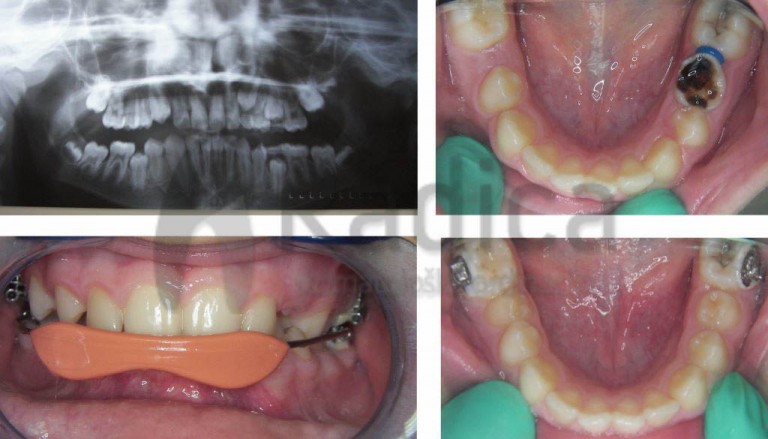

U slučaju da ipak dođe do preranog gubitka mliječnih zuba preporučuje se napraviti držače mjesta, transplatinalni i/ili lingvalni lukovi koji sprječavaju pomak „šestica“ i čuvaju mjesto za trajne nasljednike.

Nažalost, najveći broj ortodontskih pacijenata u Hrvatskoj upravo su oni koji su prerano izgubili mliječne i/ili trajne zube jer ih nisu prali niti odlazili stomatologu.

Ortodontske anomalije uzrokovane preranim gubitkom mliječnih zuba i poslije gubitkom trajnih u suvremenom su svijetu rijetka pojava, a kod nas je gotovo svako treće dijete bez trajnih “šestica”.